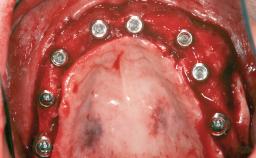

An 80-year-old female patient was referred to clinic for rehabilitation of her dentition. The patient’s medical history revealed no significant findings that would preclude routine dental and oral surgical procedures. She reported no drug allergies and was currently taking no prescription medications.

Her chief complaint was her inability to masticate efficiently due to the recent loss of her mandibular second premolars and first molars bilaterally. She expressed a desire for fixed prostheses in the shortest possible time due to her advanced age, requesting that replacement teeth should look as natural as possible. She was otherwise comfortable and not experiencing any symptoms from her teeth.

# of Teeth 4

# of Implants 4